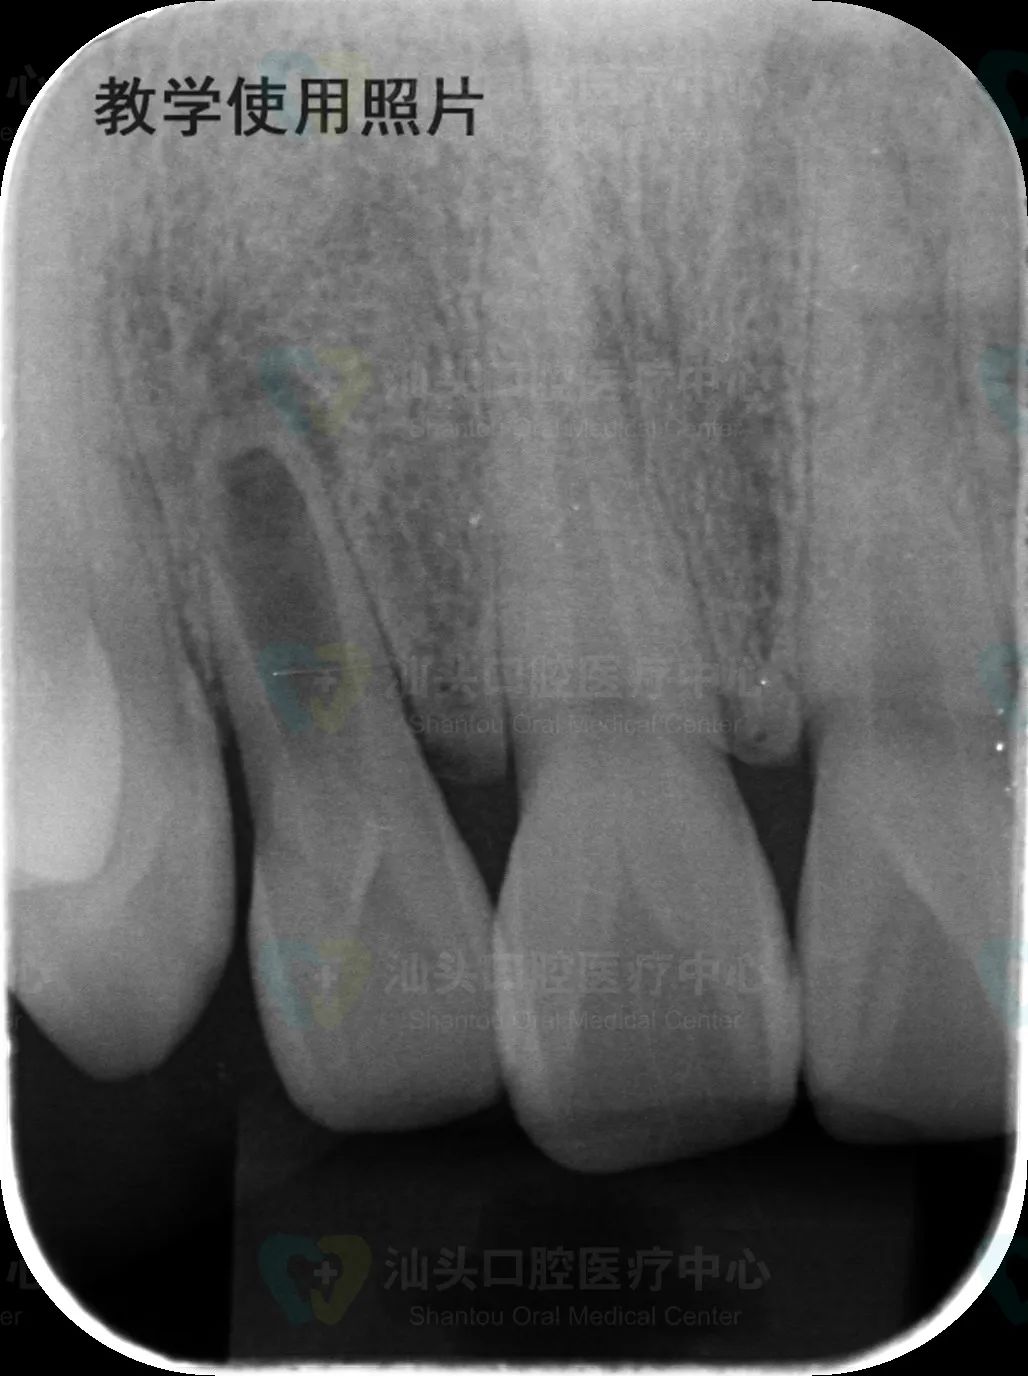

想要及时发现,就需要定期进行口腔检查。牙内吸收会导致患牙内部空腔出现扩大,拍摄小牙片,对比正常结构即可发现。

小牙片 | 牙内吸收